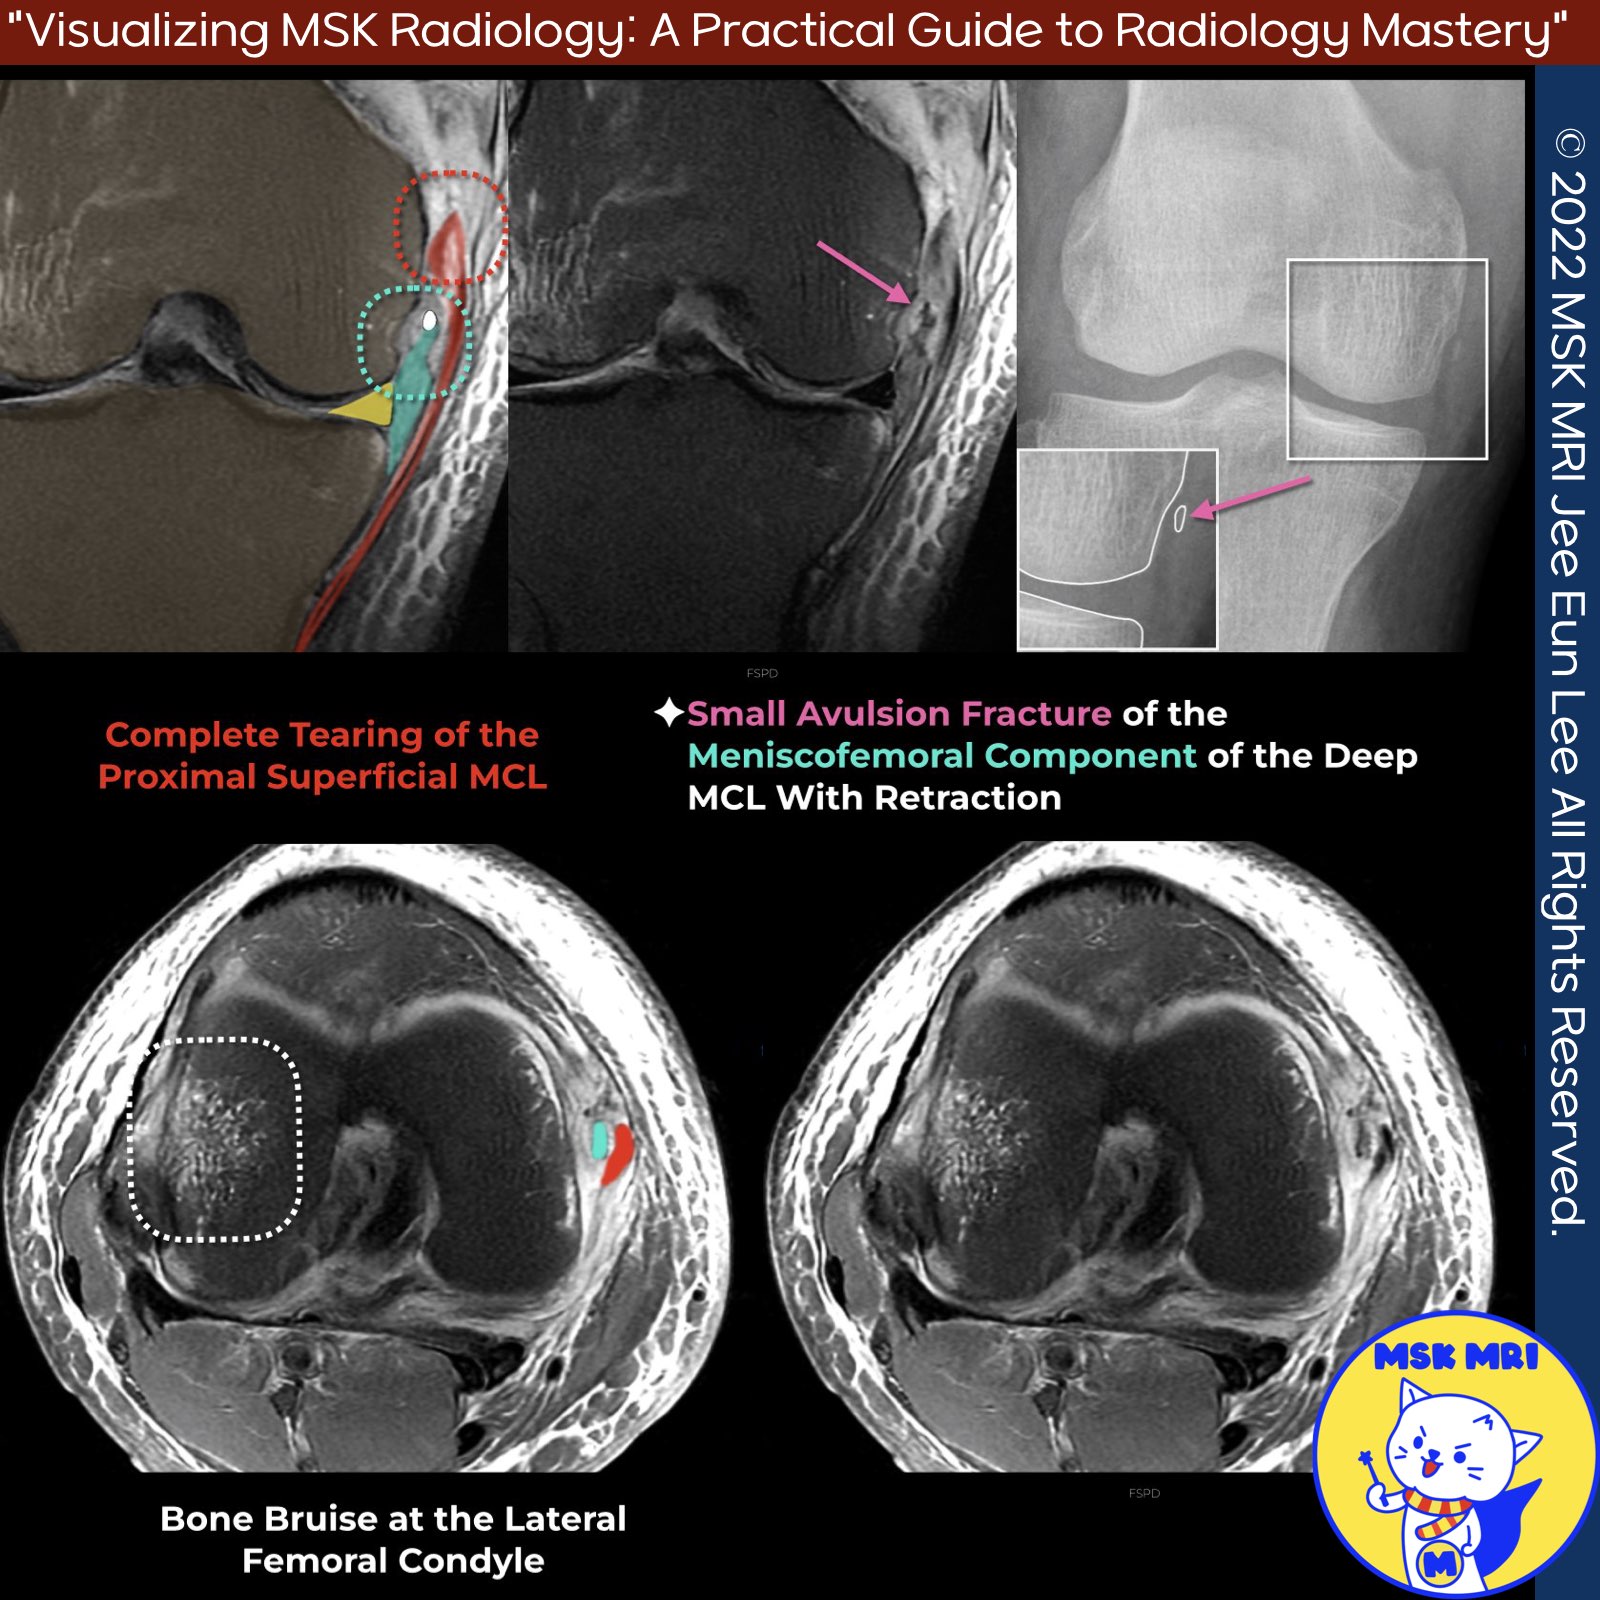

📌Deep MCL Avulsion Injury: Symptoms and Types

✅ Symptoms:

- Isolated meniscofemoral ligament tear: Chronic knee pain (no instability)

- Meniscotibial ligament tear: Knee instability, medial meniscus extrusion

- May mimic meniscal tear symptoms

✅ Injury Types:

1️⃣ Meniscofemoral Ligament Injuries

- Rare avulsion fractures in adults

- More prone to sprains/tears due to longer, thinner structure

2️⃣ Meniscotibial Ligament Injuries

- More common avulsion fractures

- Thicker, shorter ligament more likely to avulse bone at attachment site

- Known as "reverse Segond fracture" if tibial avulsion

✅ Current Case:

- Complete proximal superficial MCL tear

- Femoral avulsion fracture of meniscofemoral ligament (deep MCL)

- Meniscofemoral ligament thickened and distally retracted

- Better visualized on CT/radiography than MRI

- If meniscotibial avulsion would be termed "reverse Segond fracture"